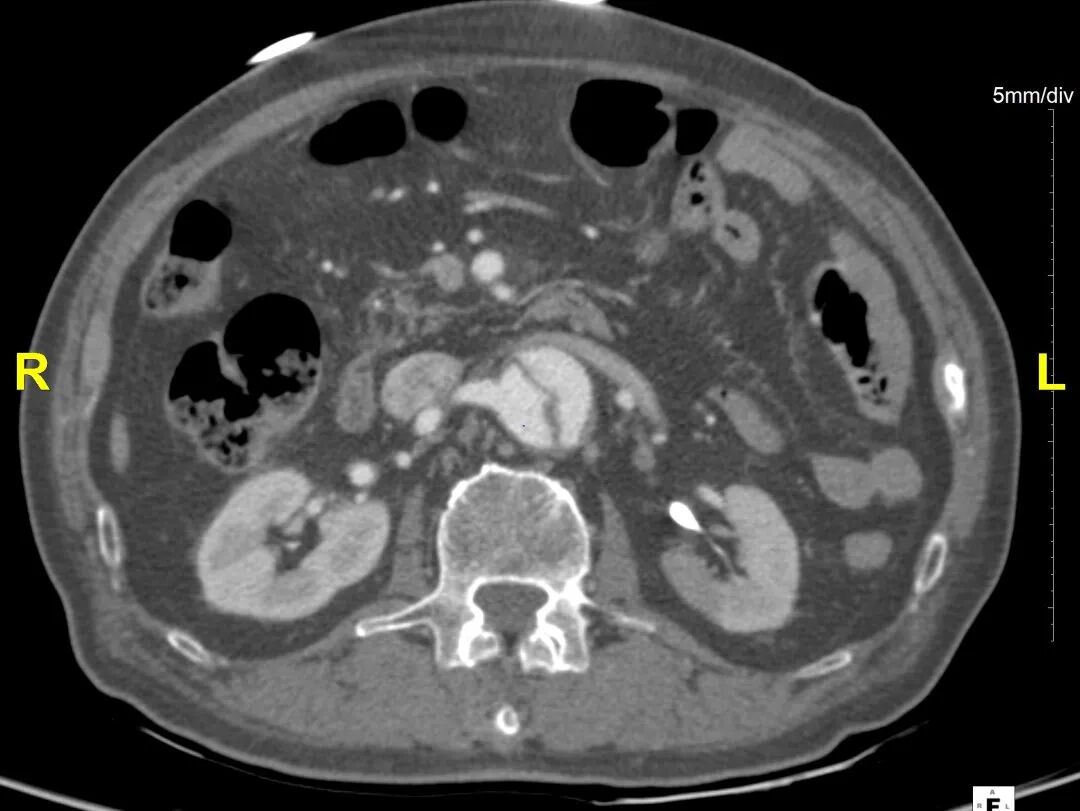

病例CTA详解

横断面影像

1)内膜多处撕裂,真腔严重狭窄。

2)CA假腔供血,SMA双腔供血,LRA假腔供血,RRA真腔供血,腹主段闭塞。